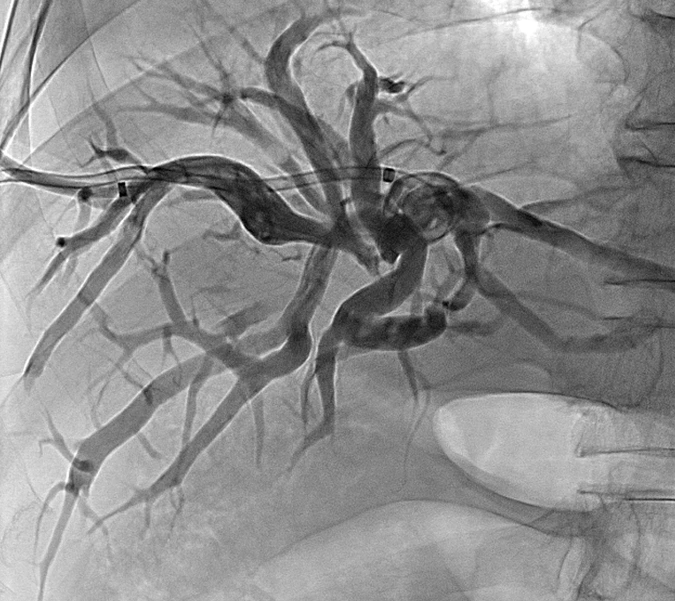

胆道粒子支架是将金属胆道支架与放射性粒子(通常为碘-125,¹²⁵I)相结合的一种创新型介入治疗手段。

机械支撑作用

金属支架植入后可即刻扩张狭窄的胆道,恢复胆汁引流通畅,迅速缓解黄疸症状。

1、胆管癌(肝门部胆管癌、远端胆管癌)

2、胰头癌侵犯胆道

3、转移性肿瘤导致的胆道梗阻

4、其他无法手术切除的恶性胆道狭窄